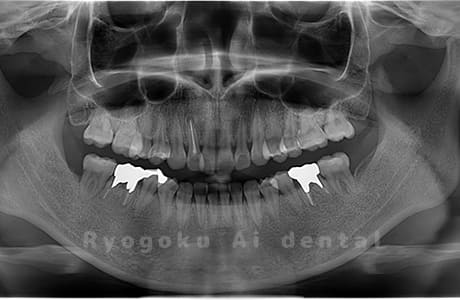

Case02

- 原因

- 下顎の水平埋伏智歯

- 治療内容

- 下顎の水平埋伏智歯を抜歯

<リスク・副作用>

手術後は痛み、腫れ、痺れなどの副作用が生じる場合があります。